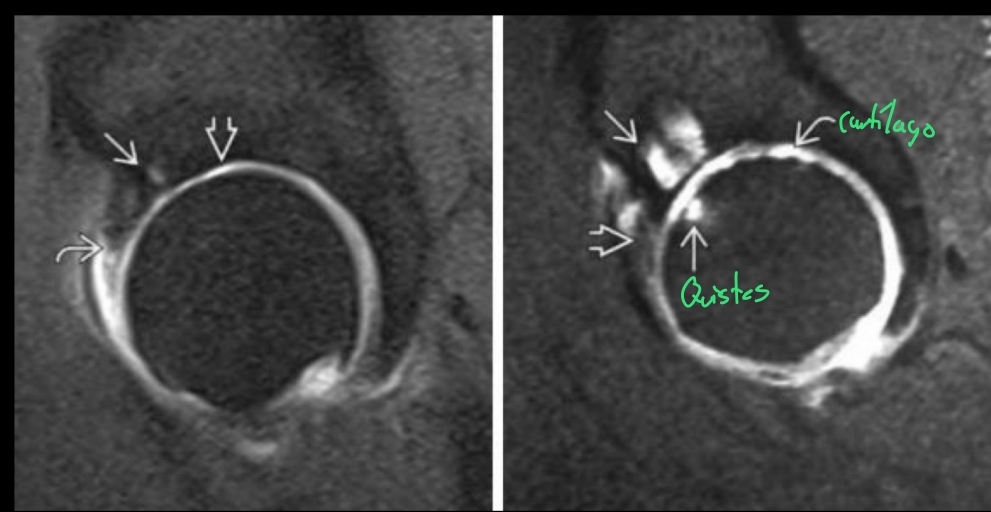

Qué se ve en la RM en la coxartrosis que no se puede ver directamente en una TC o Rx?

A

• Permite evaluar cartílago (Daño temprano)

Qué se ve en la RM de una gonartrosis?

• Permite evaluar el cartílago

• Se puede ver un derrame articular

• Mismos datos que en TC y Rx